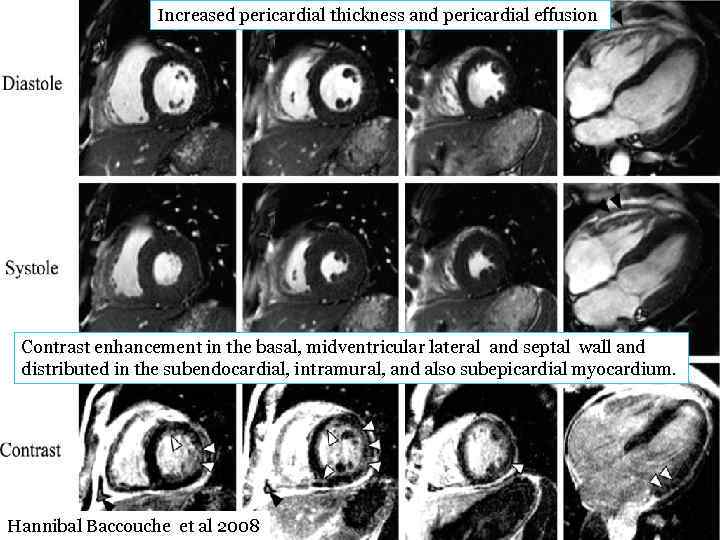

Transthoracic echocardiogram (TTE). Systolic as well as diastolic images of apical long axis (4 CH) and parasternal short axis (SAX) are displayed. No pericardial effusion could be detected, and no information on myocardial involvement in suspected Churg-Strauss syndrome could be obtained by TTE. Hannibal Baccouche et al 2008

Increased pericardial thickness and pericardial effusion Contrast enhancement in the basal, midventricular lateral and septal wall and distributed in the subendocardial, intramural, and also subepicardial myocardium. Hannibal Baccouche et al 2008